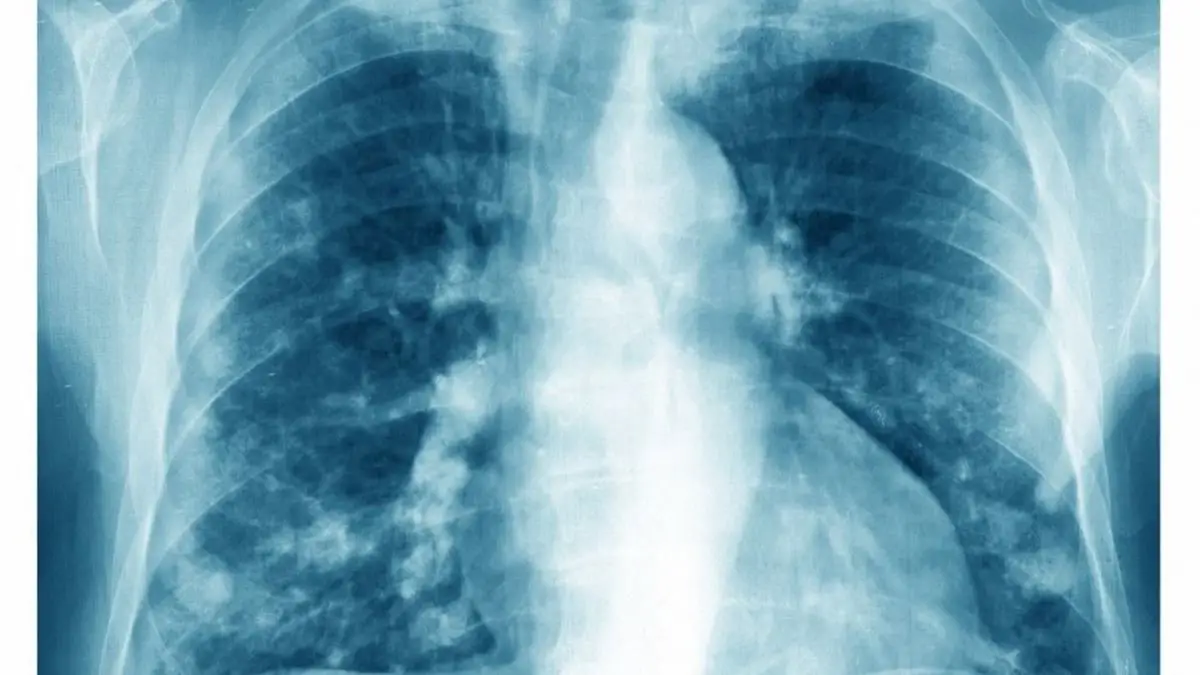

Egyre több olyan embernél diagnosztizálnak tüdőrákot, aki soha nem dohányzott. A szakértők szerint ebben a légszennyezésnek döntő szerepe lehet. Különösen az adenokarcinóma vált a leggyakoribb altípussá a nemdohányzók körében.

A Nemzetközi Rákkutatási Ügynökség (IARC) legfrissebb adatai szerint a tüdőrákos megbetegedések egyre nagyobb hányada érinti azokat, akik életük során nem dohányoztak. Bár a cigarettázás továbbra is a legfőbb kockázati tényező, egyre több kutatás utal arra, hogy a légszennyezés kulcsszerepet játszhat a daganat kialakulásában - írja az origo.hu.

A 2022-es adatok alapján világszerte a tüdőrákos esetek jelentős részét adenokarcinóma teszi ki: a férfiak 45,6%-a és a nők 59,7%-a ebbe a csoportba tartozik.

Különösen aggasztó, hogy a nemdohányzók körében az esetek mintegy 70%-a ebbe az altípusba sorolható.

A jelenség elsősorban Kelet-Ázsiát érinti, különösen Kínát, ahol a nagyvárosi légszennyezés kiemelkedően magas.

A tüdőrák továbbra is a legtöbb halálozást okozó daganattípus. 2022-ben körülbelül 2,5 millió új megbetegedést regisztráltak. Bár a férfiaknál az előfordulás mérséklődni látszik, a nőknél az elmúlt évtizedekben folyamatosan emelkedett, és a két nem közötti különbség egyre inkább csökken.